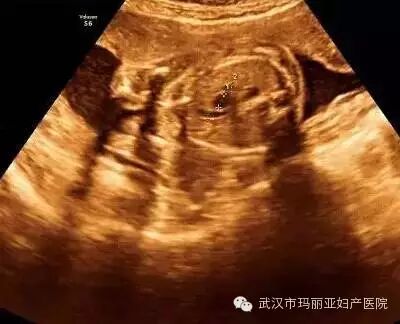

武汉玛丽亚妇产医院引进的世界领先的美国GE-E8四维彩超设备室目前世界上最先进、分辨率最高的彩色超声设备,具有即时立体成像、清晰准确的特点。

它能够多方位、多角度地观察宫内胎儿的生长发育情况,为早期诊断胎儿先天性体表畸形和发育异常提供科学依据。还能对胎儿的体表进行检查,如唇裂、脊柱裂、大脑、肾、 骨骼发育不良等,以便尽早的进行治疗。

玛丽亚美国GE-E8四维彩超排畸成功案例

案例四:轮状胎盘